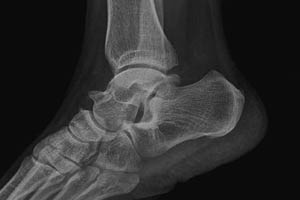

X线检查:患者左足周围软组织肿胀,局限性骨质轻微损坏,出现明显痛风结石。